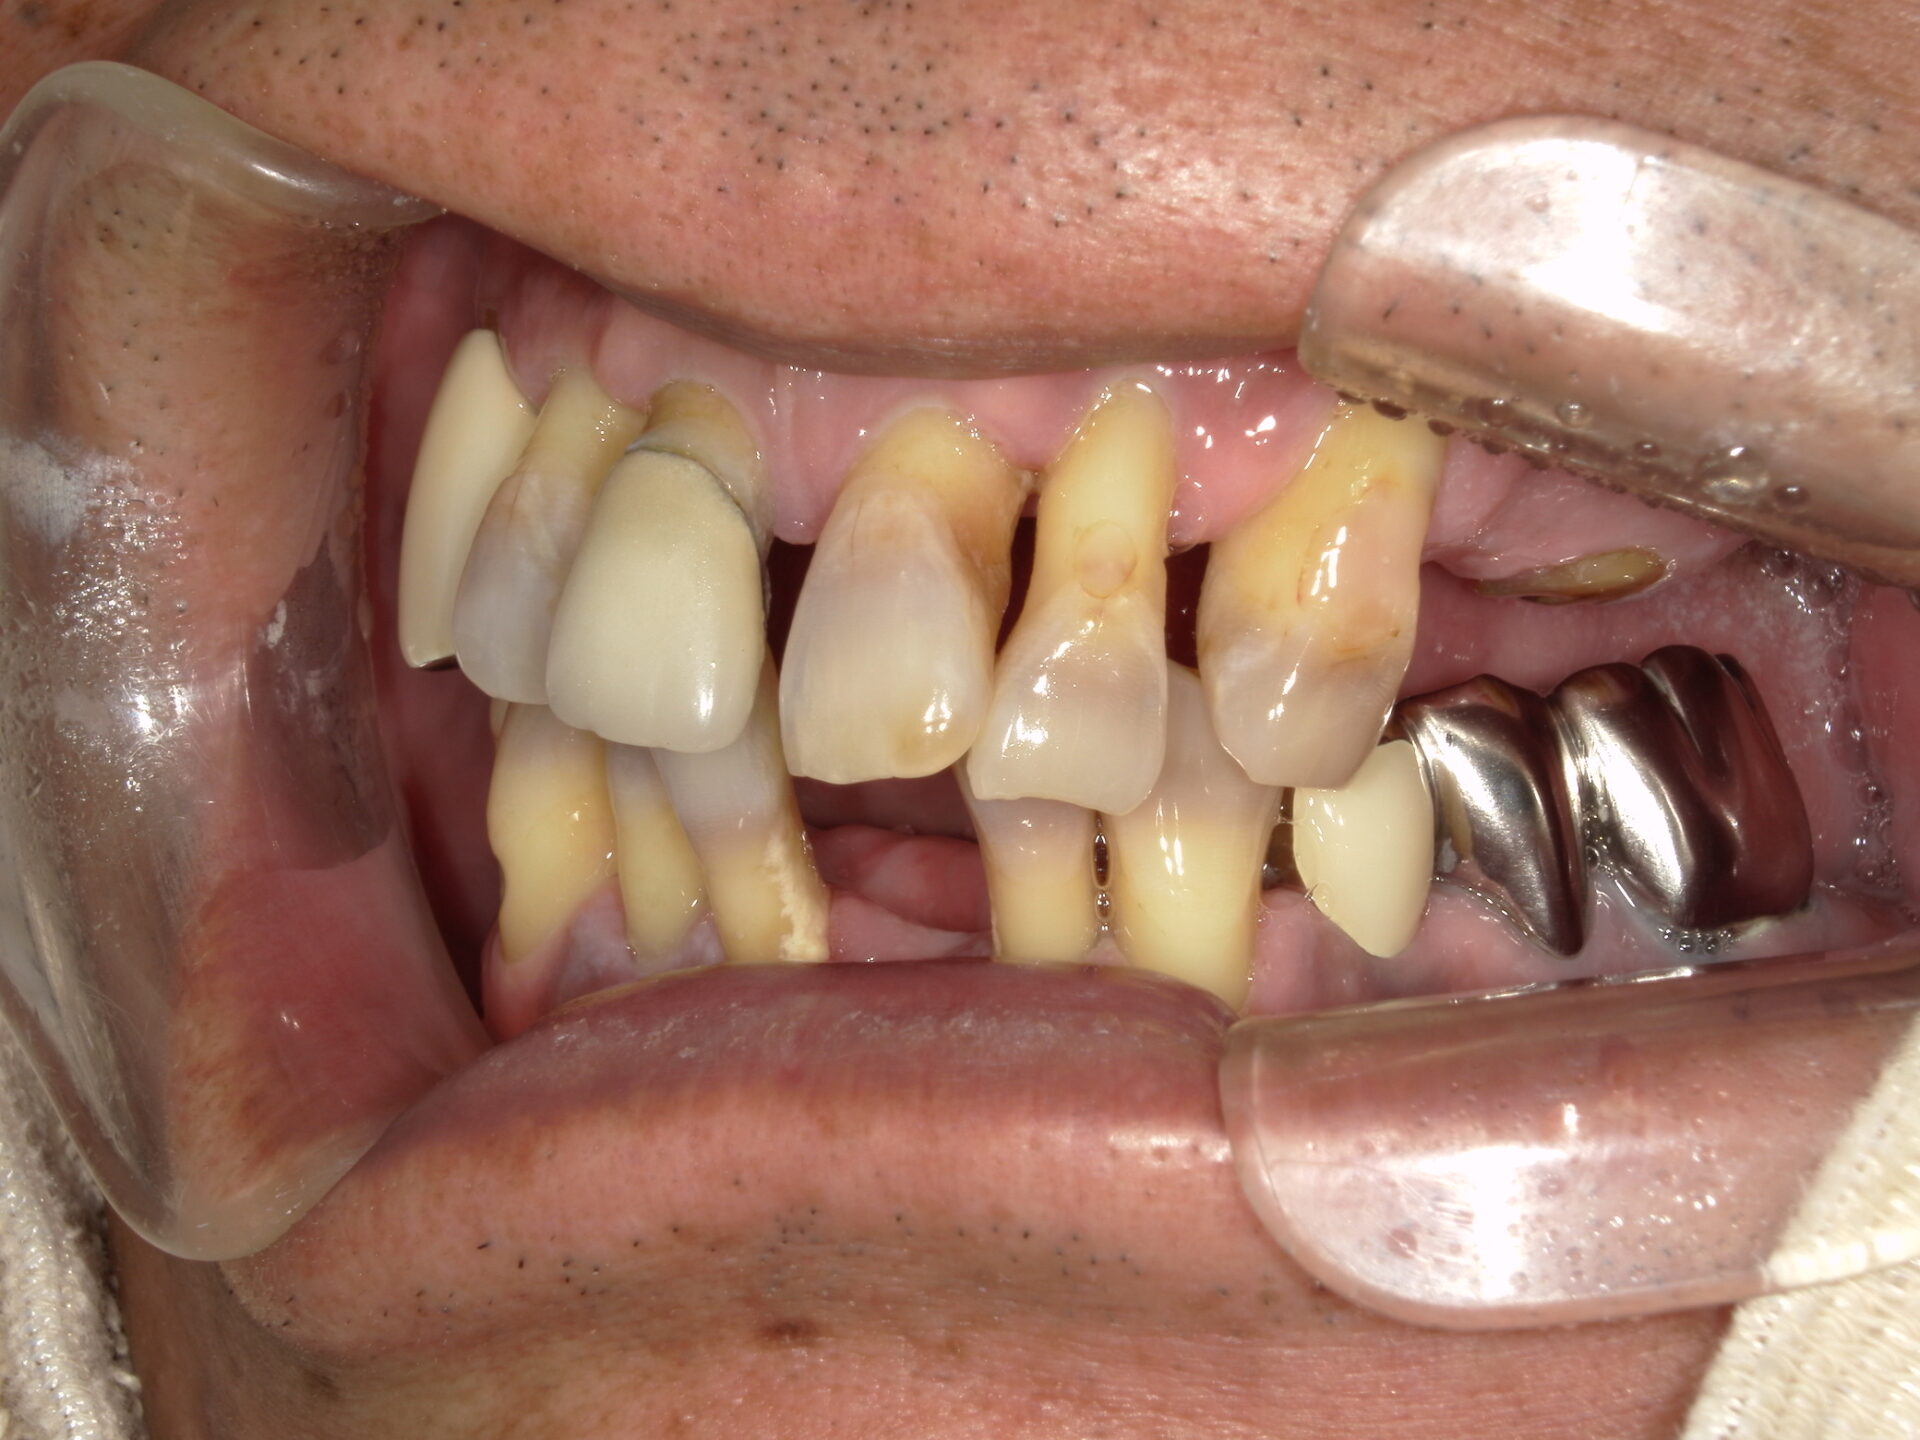

before

after

患者さんの年齢 50代 男性 症状 何も噛めない 治療内容 インプラント治療(オールオン4) 費用 費用900万(税抜) 治療期間・回数 治療期間2年・通院回数12回 メリット なんでも噛めるようになる 見た目が綺麗 デメリット・リスク 骨造成などで費用が増える場合がある - インプラント治療